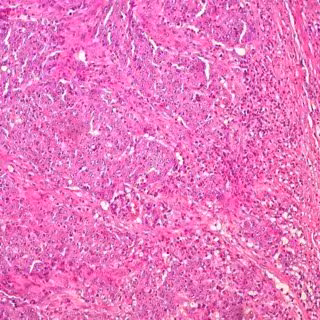

Archivo - Cáncer de colon

Archivo - Cáncer de colon - UCM - Archivo